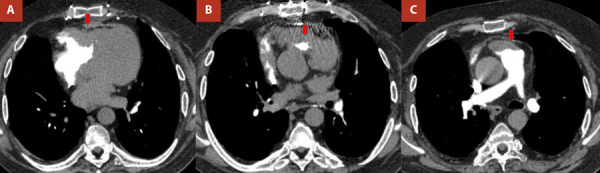

We present the case of a 42-year-old male patient with a history of bilateral lung transplantation and chronic graft dysfunction. The patient presented to the adult emergency department due to acute heart failure. During his stay in the emergency room and in outpatient follow-up, cardiac multi-imaging led to the diagnosis of double-chambered right ventricle with associated hypertrophic cardiomyopathy. Given the presence of advanced lung disease and poor adherence to immunosuppressant medication as well as clinical follow-ups, the patient was deemed unsuitable for re-lung transplantation. The optimization of his immunosuppressive medication was prioritized, and beta-blockers were added as part of the treatment for dynamic right ventricular outflow obstruction. He was referred to pulmonary rehabilitation, currently showing a partially favorable evolution to functional class II.